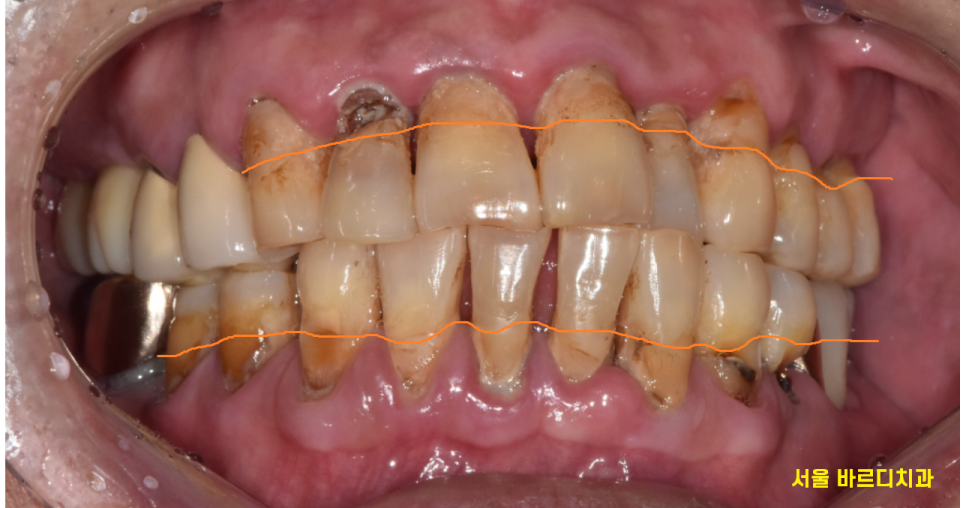

구강 내 사진을 보시면

전반적으로 치아가 길어보이죠~?

주황색 라인까지 잇몸이 덮여 있어야하는데

잇몸뼈가 내려가면서

치아도 길어져 보이는거죠~

치아 뿌리 부분만 붙잡고 있으니

위아래 치아 흔들림과 함께

통증이 있었습니다.